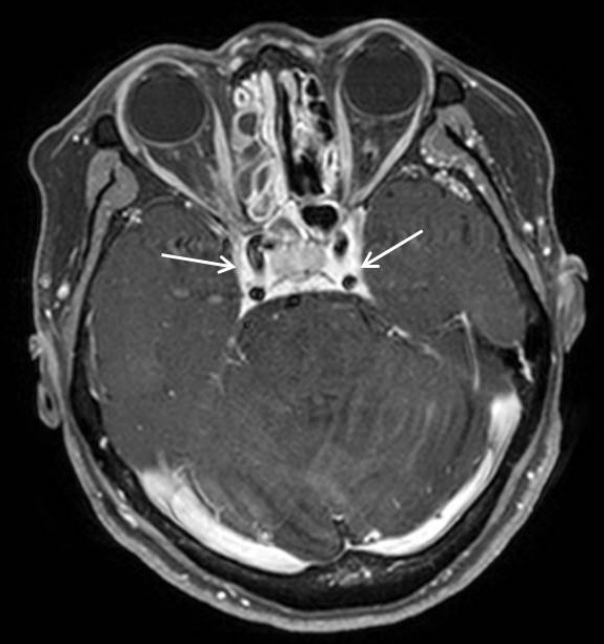

58세 여자 환자가 내원 2일 전부터 시작된 두통과 가벼운 비회전성 어지럼증으로 본원 신경과에 내원하였다. 환자는 기저 질환이 없이 건강하던 자로 두통은 간헐적으로 머리 전반적인 부위에서 발생한다고 하였고, 신경학적 검사상 이상소견은 보이지 않았다. 말초성 현훈 감별 위해 두부충동 검사, 두위충동 검사, 두위안진, 냉온교대 온도안진 검사(bithermal caloric test) 등을 시행하였으나 특이 소견은 관찰되지 않았다. 이에 추가 정밀 검사 및 보존적 치료를 위해 신경과로 입원하였다. 일반 혈액 검사에서 백혈구는 10.07×103/uL에 중성구 81%, 적혈구 침강속도는 86 mm/hour로 증가되었으나 그 외 검사상 다른 이상 소견은 보이지 않았다. 뇌 확산 자기공명영상(brain MR diffusion)을 촬영하였고, 허혈성 병변 및 뇌실질의 병변은 확인되지 않았으나, 우측 사골동과 접형동 부비동염 의심 소견이 확인되었다. 입원 2일째 환자가 갑작스러운 복시와 우측 안검하수를 호소하여 시행한 안과 검진상 시력, 안압 등은 정상이었고, 안구 운동 시 우안의 내전, 외전, 상전, 하전 제한과 안검하수가 관찰되었다(Fig. 1). 우측 사골동과 접형동 부비동염 및 우측 동안 및 외전 신경 마비 의심하에 부비동 전산화단층촬영(paranasal sinus CT, PNS CT) 및 후두와 자기공명영상(posterior fossa MRI)을 시행하였다. MRI에서 팽윤된 양측 해면정맥동과 주변 경막의 비후 소견이 관찰되었으며, 상기 소견은 우측이 더 심하였고 혈전 형성은 보이지 않았다(Fig. 2). PNS CT상 우측 전두동, 상악동, 사골동과 접형동의 연부조직음영이 있었으며, 좌측 상악동, 사골동과 접형동에도 일부 음영증가 소견이 보였고, 골결손은 보이지 않았다(Fig. 3). 환자는 코막힘, 후각 감퇴, 콧물, 재채기 등의 비증상은 호소하지 않았으나, 비강 검사상 좌측 비중격 만곡증 및 양측 비용 소견이 관찰되었다. 임상학적 양상과 영상 소견을 종합한 결과 급성 부비동염에 병발된 해면정맥동혈전염으로 인한 우측 동안 및 외전 신경마비로 의심되어 부비동 내시경 수술과 항생제와 스테로이드 정맥주사(ampicillin/sulbactam 1.5 g tid, cefotaxime 1 g tid, metronidazole 500 mg tid, dexamethasone 5 mg bid)를 진행할 것을 계획하였다. 입원 3일째, 전과 후 비중격 교정술과 양측 부비동 내시경술을 시행하였다. 전신마취하에 비중격 교정술 후 우측 전두동, 상악동, 사골동의 비용과 병변 점막을 제거하면서 자연공을 충분히 넓혔으며, 접형동 개구술을 통해 배농을 시행하였다(Fig. 4). 좌측 사골동, 상악동, 접형동도 비용과 병변 점막 제거 및 개방술을 진행하였다. 술 후 1일째, 두통, 어지럼증과 안검하수는 호전되었으나, 복시는 지속되는 양상이었다. 술 후 5일째에 안검하수 증상은 개선되었고, 우측 주시시 여전히 복시를 호소하였다. 술 후 7일째 퇴원하고 경구 항생제, 경구 스테로이드, 비강 스테로이드제(amoxicillin/clavulanate potassium 1 g bid, prednisolone 10 mg bid, fluticasone 5 mg qd)를 3주간 사용하였다. 추적 관찰하기 위해 촬영한 PNS CT상 양측 상악동, 사골동과 접형동의 부비동염 양상은 대부분 호전되었다(Fig. 5). 술 후 1개월째 안과 진료를 통해 복시가 개선된 것으로 확인되었고, 수술 2개월경 시행한 안과 검진상에서 외안근 기능이 모두 정상화된 것을 확인할 수 있었다(Fig. 6).

해면정맥동 혈전염의 진단을 위해서는 전산화단층촬영이 가장 중요하며 우선적으로 시행되어야 한다. 이를 통해 접형동의 함기화 정도 및 골미란 여부와 접형동 병변과의 관계성을 확인해 볼 수 있으며, 골미란 소견이 있거나, 시력 저하, 복시, 안검하수 등 뇌신경마비 소견이 보이는 경우 뇌 자기공명영상을 추가로 시행해야 한다[8,9]. 해면정맥동 혈전염의 자기공명영상 소견으로는 해면정맥동의 비대칭적 팽창과 혈전 형성을 시사하는 해면정맥동 내 불규칙한 다발성 충만 결손(filling defect), 해면정맥동 내 내경동맥(intracavernous internal carotid artery)의 현저한 내경 감소 및 해면정맥동 주위 경막의 조영증강 등이 있고, 상안정맥 확장이나 안구 돌출 양상도 보일 수도 있다[5,7,10]. 본 증례에서는 뇌 자기공명영상에서 양측 해면정맥동의 팽창 및 주변 경막의 조영 증강 소견을 보여 해면정맥동 병변을 의심해볼 수 있었으며, 충만 결손은 확인되지 않아 혈전은 뚜렷하게 생성되지 않았음을 확인하였다. 영상 소견에서는 양측 해면정맥동 혈전염이 확인되었지만, 환자는 우측에서만 안증상을 보였다. 해면정맥동 혈전염은 양측으로 교통되어 있어서, 원인 질환이 일측이라도 양측으로 금방 전파될 수 있다[7,11]. 본 증례에서는 우측 사골동염과 접형동염이 상대적으로 심하였기 때문에 안증상이 우측에서 먼저 확인되었고, 빠른 치료가 없었으면 좌측 안증상도 발생했을 가능성이 있다고 생각된다.